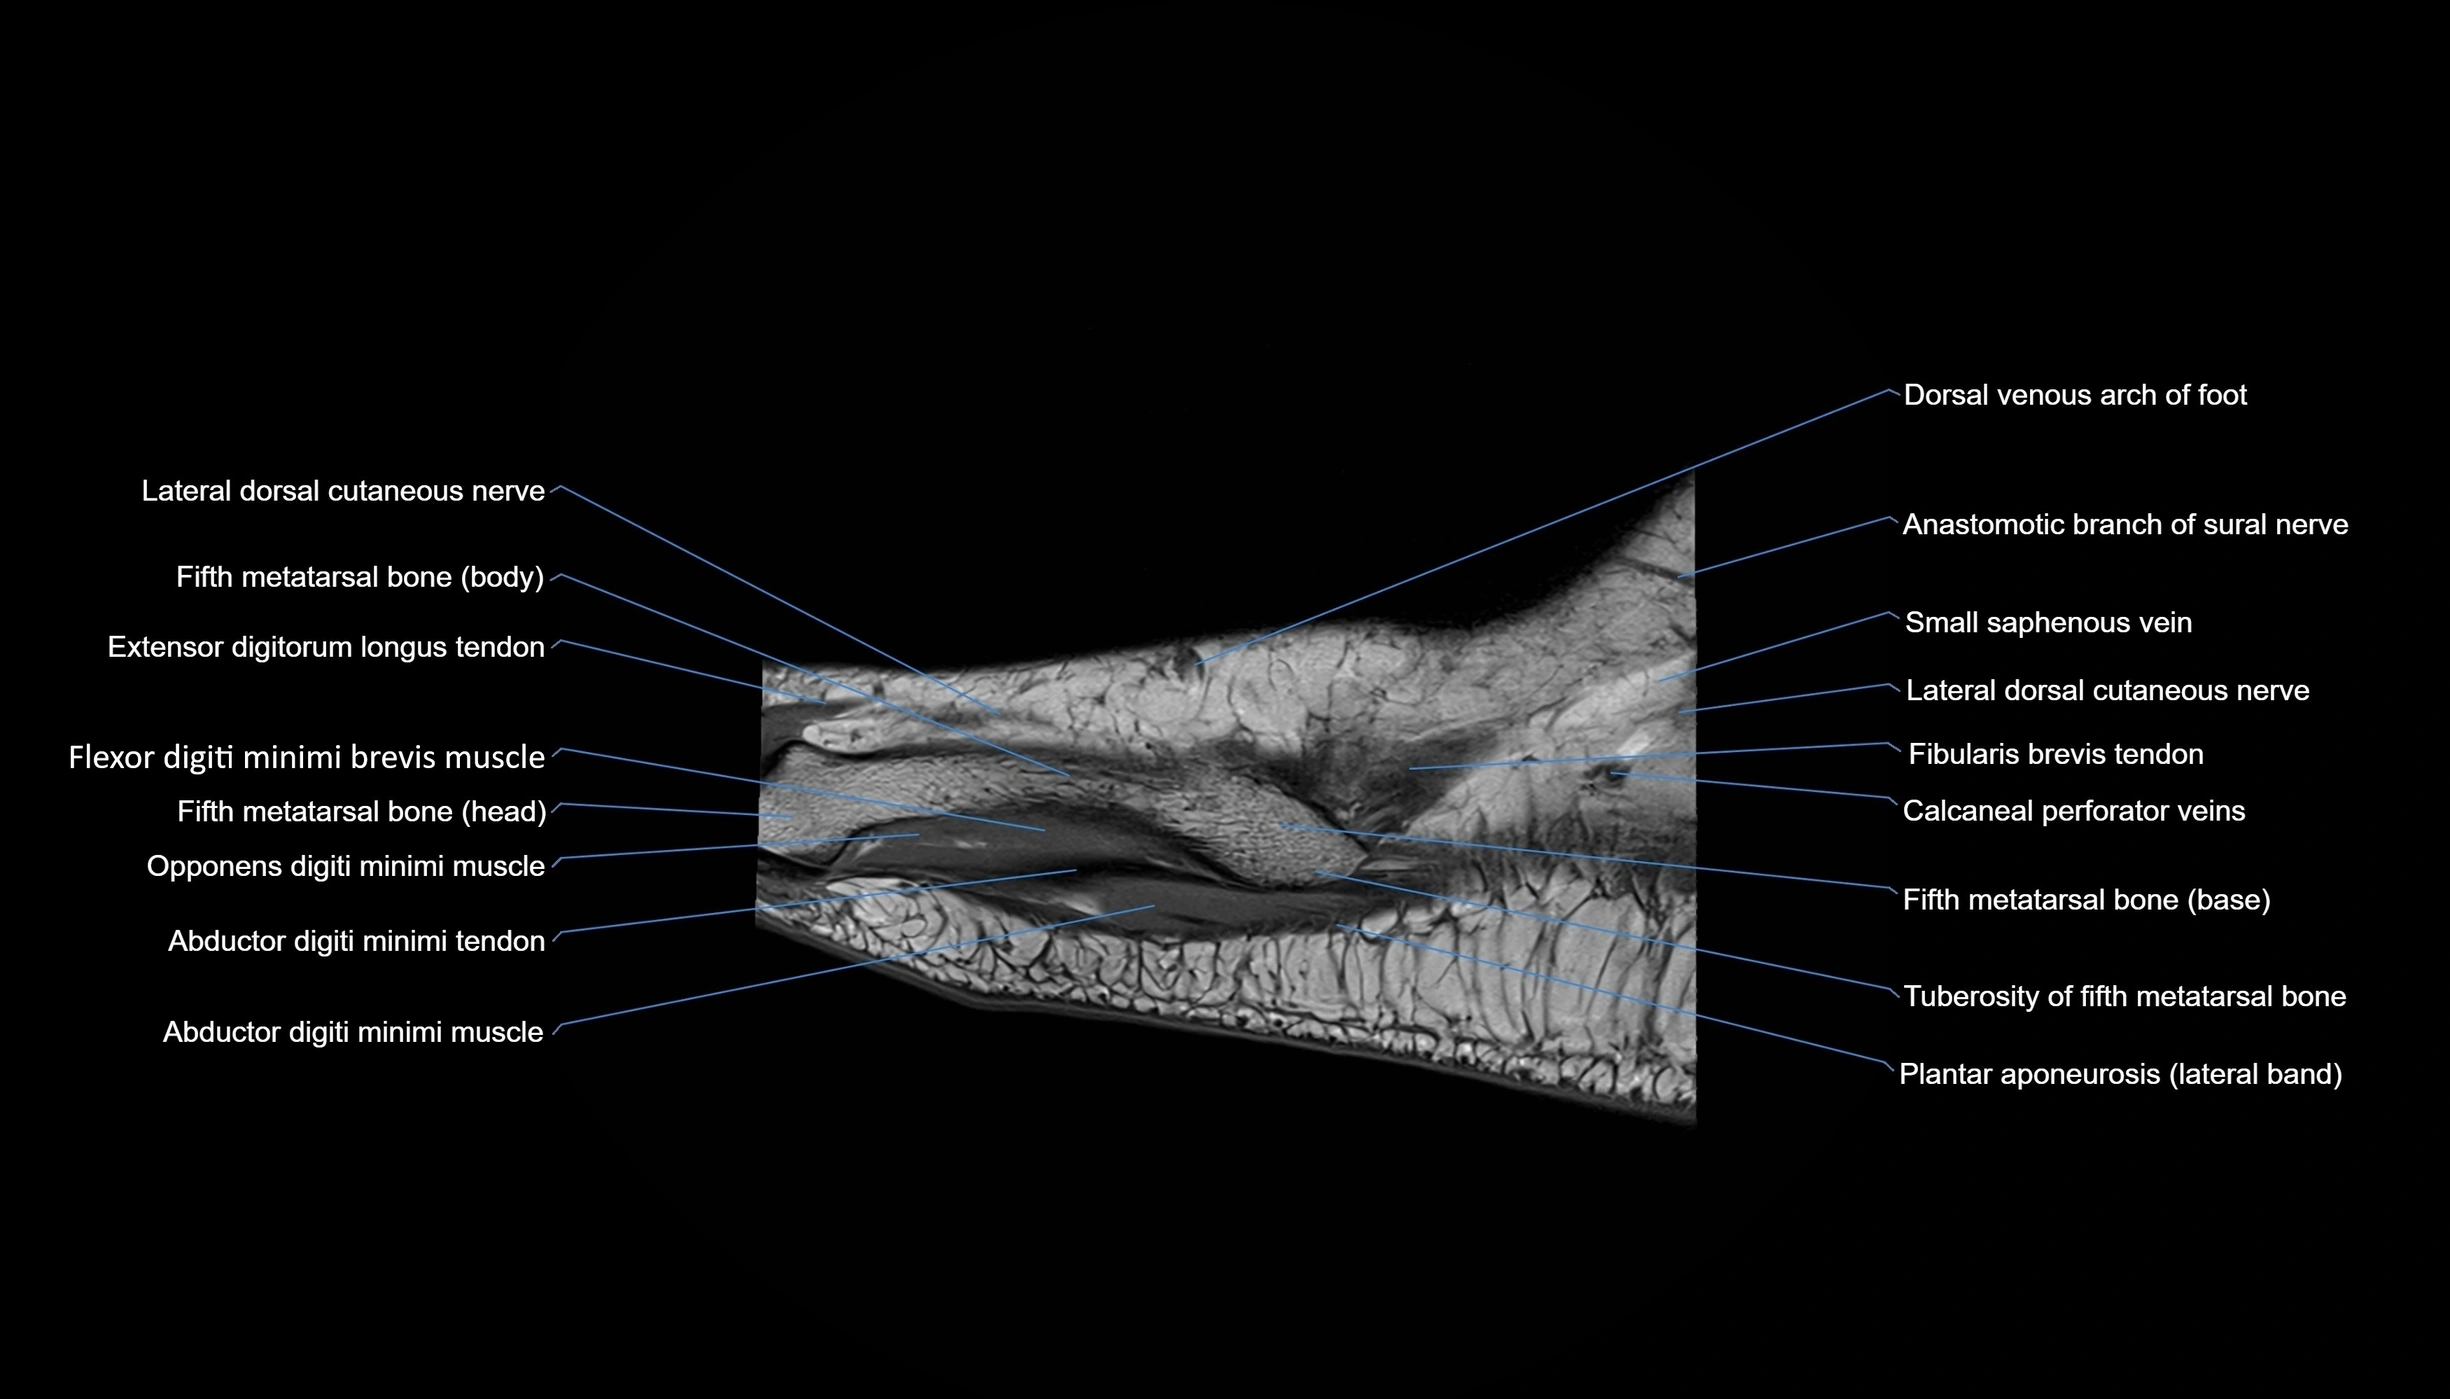

MRI image